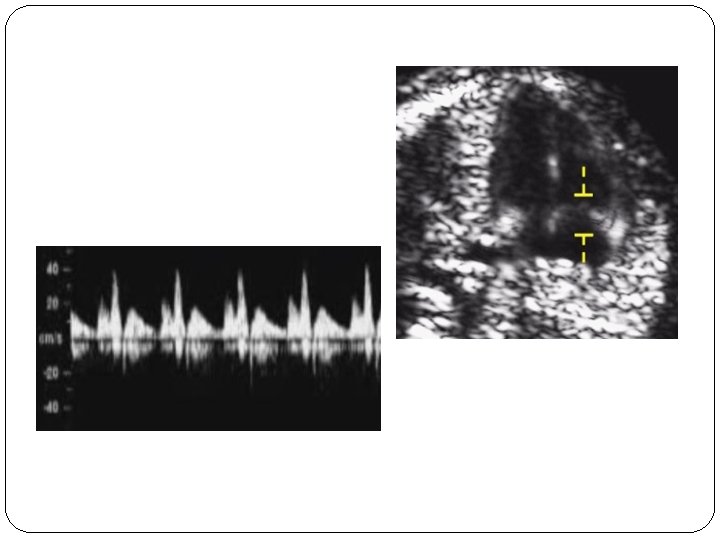

TR � The magnification of the image should be such that the fetal thorax occupies most of the image. � An apical four-chamber view of the fetal heart should be obtained. � A pulsed-wave Doppler sample volume of 2. 0 to 3. 0 mm should be positioned across the tricuspid valve so that the angle to the direction of flow is less than 30 degrees from the direction of the interventricular septum.

TR � Tricuspid regurgitation is diagnosed if it is found during at least half of the systole and with a velocity of over 60 cm/s, since aortic or pulmonary arterial blood flow at this gestation can produce a maximum velocity of 50 cm/s. � The tricuspid valve could be insufficient in one or more of its three cusps, and therefore the sample volume should be placed across the valve at least three times, in an attempt to interrogate the complete valve

�The incidence of tricuspid regurgitation is related to NT and CRL as well as aneuploidy, being more common when the NT is high and the CRL is low. �If the risk is more than 1 in 50 and tricuspid flow is normal the risk does not change. �If the risk is 1 in 50 to 1 in 1, 000 and the tricuspid flow is normal the risk is usually reduced. If there is tricuspid regurgitation the risk is always increased.

� In addition, there is an increased risk for cardiac defects and therefore such patients should have a follow up specialist fetal cardiac scan.

Ductus venusus flow �The magnification of the image should be such that the fetal thorax and abdomen occupy the whole image. �The pulsed Doppler sample volume should be small (0. 5 -1. 0 mm) to avoid contamination from the adjacent veins, and it should be placed in the yellowish aliasing area.

Ductus venusus flow �The insonation angle should be less than 30 degrees. �The filter should be set at a low frequency (50 -70 Hz) so that the a-wave is not obscured.

Contamination by the umbilical vein (may hide an absent a-wave/truncated V line)

Contamination by the IVC and HVs (may mimic a reversed a-wave/Two V shape line)